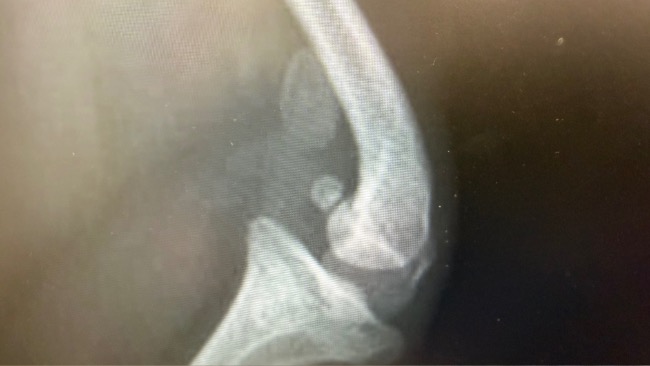

Zdiagnozowano u niej zwichnięcie rzepki czwartego stopnia. To najcięższa postać tej choroby. Rzepka w ogóle nie znajduje się w bloczku, co uniemożliwia normalne poruszanie się i powoduje stałe cierpienie. Bez leczenia jej stan będzie się tylko pogarszał.